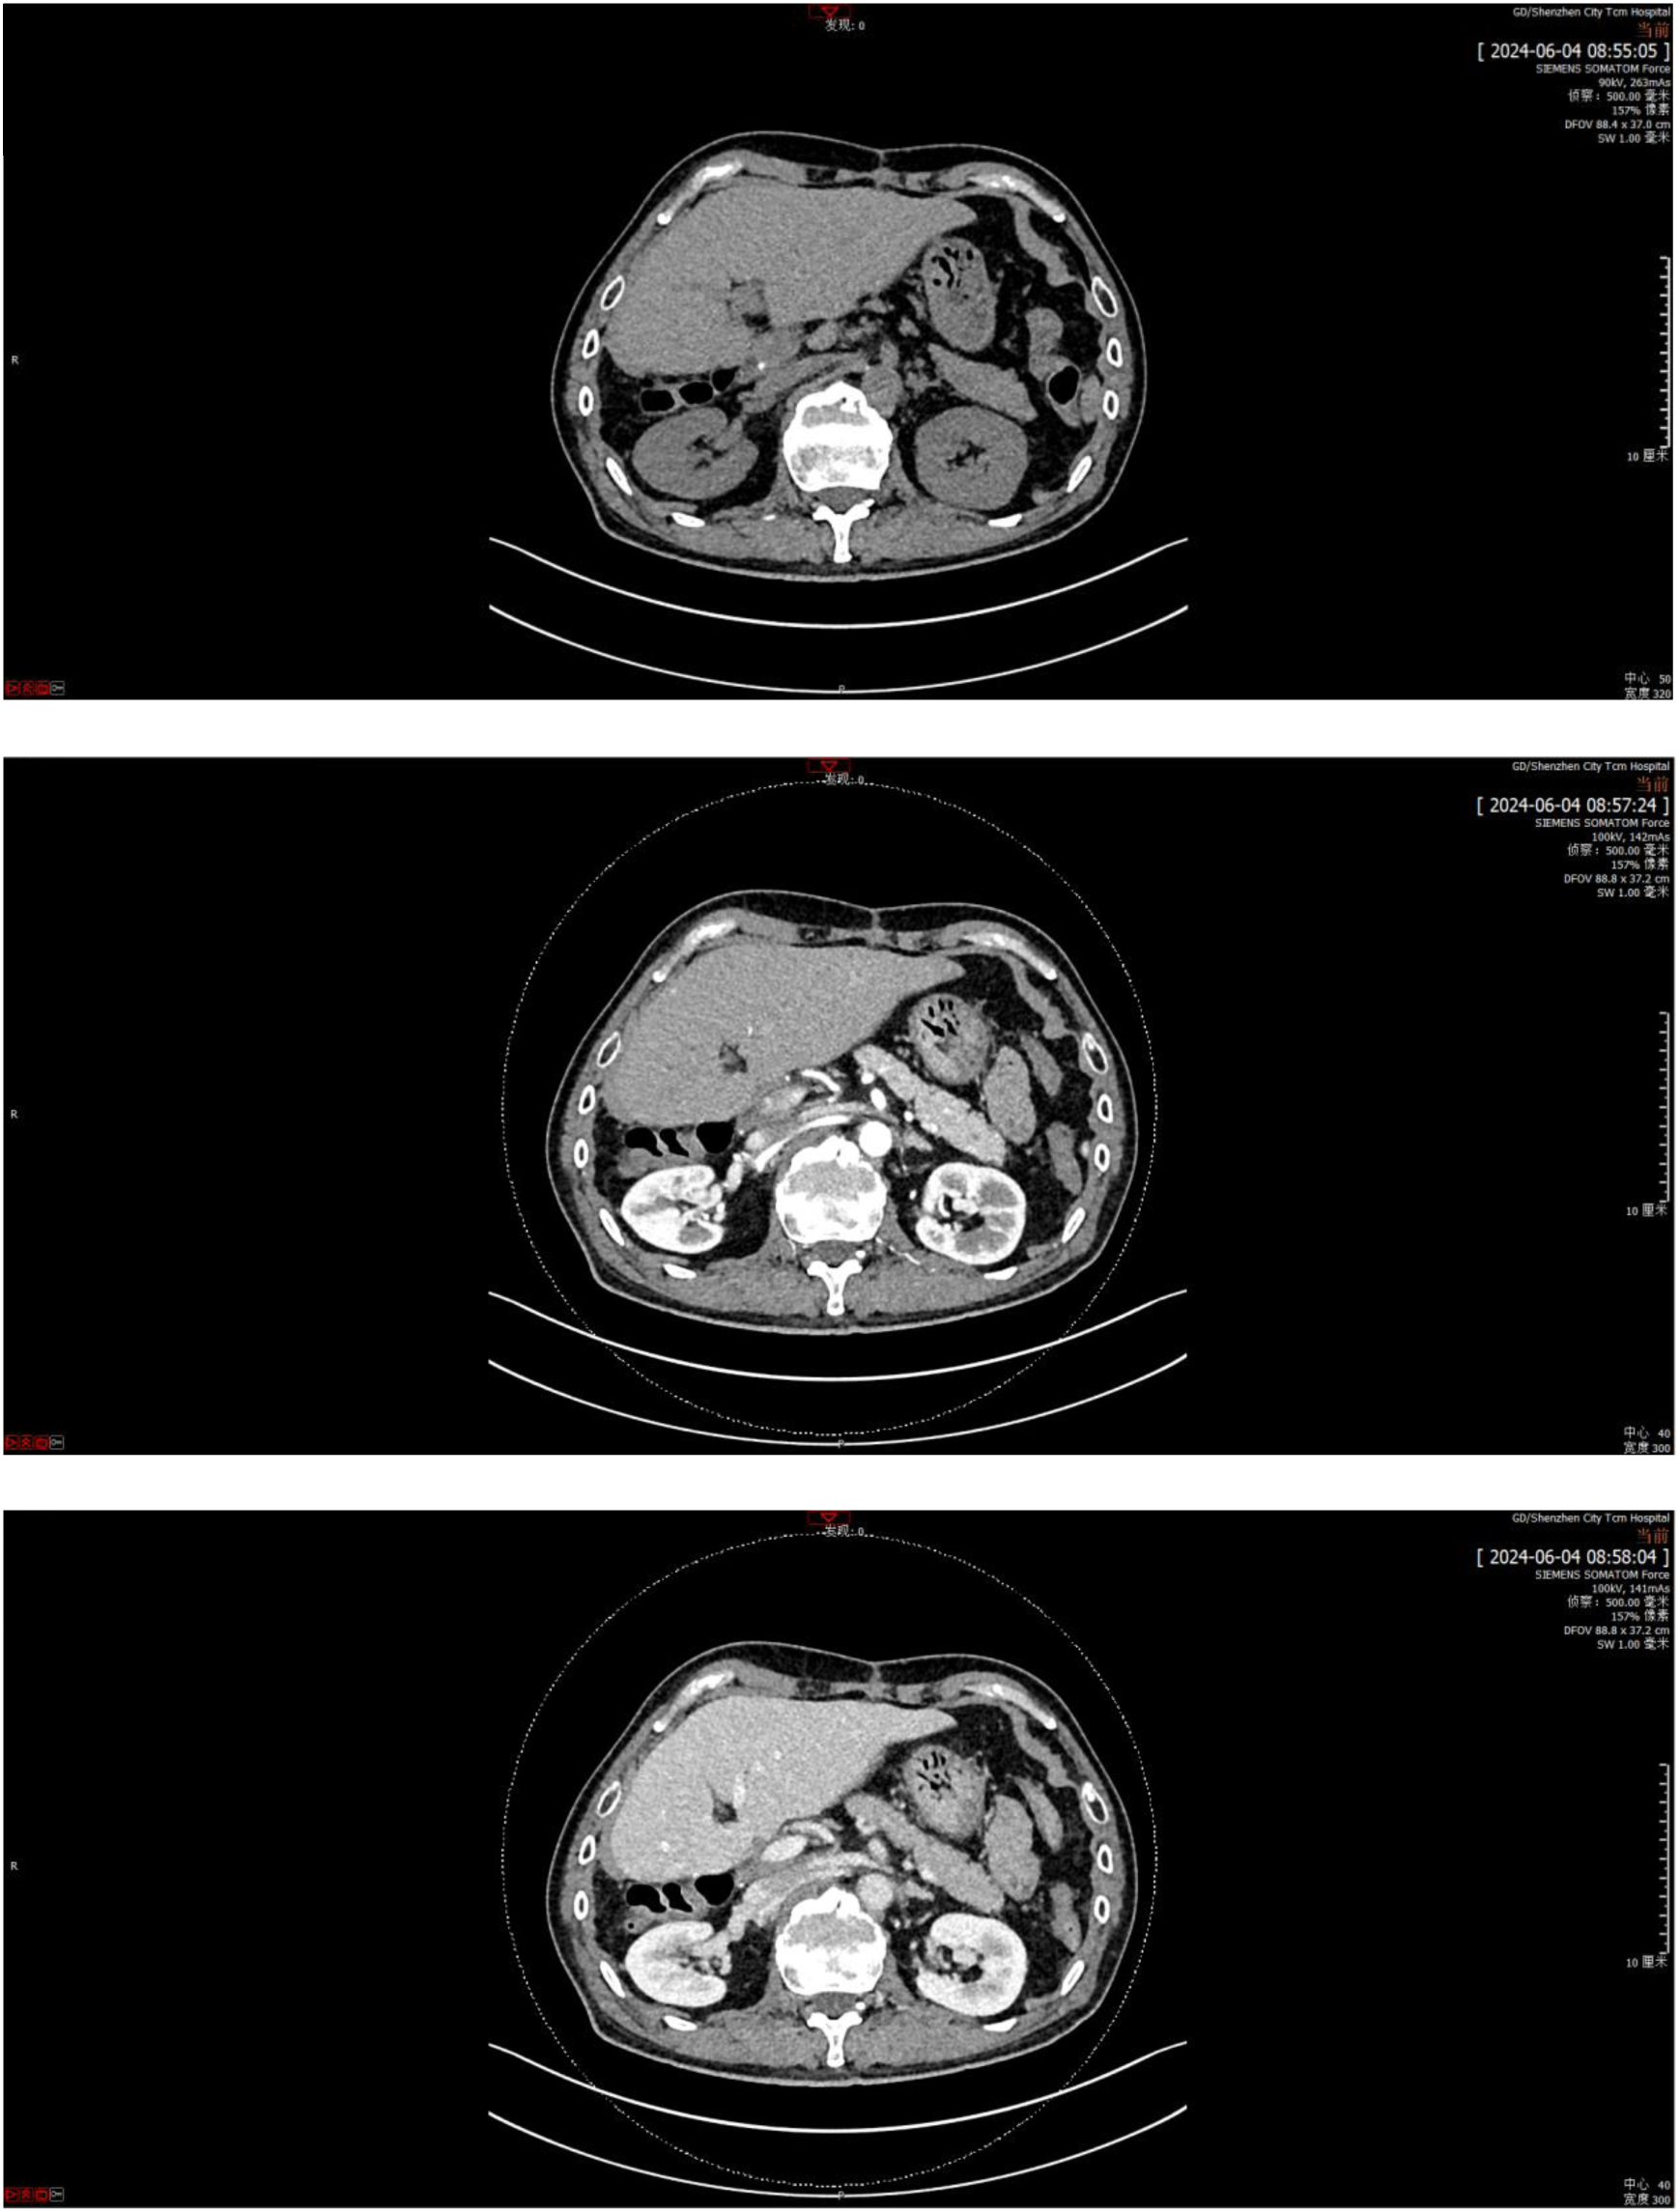

The first stage of ALPPS was performed in September 2023, consisting of cholecystectomy, right portal vein ligation, and right liver parenchymal division. Full body PET-CT images of the patient were shown in Figure 3. On day 37 post-surgery, reassessment showed improved liver function, with an ICG R15 of 5.8% and residual liver volume of 55.14% (Figure 2B). In October 2023, the second stage involved right hepatectomy and lymph node dissection. Pathological analysis confirmed moderately differentiated ICC with a tumor size of 65 mm × 60 mm × 40 mm, >80% tumor necrosis, and negative margins. No metastatic carcinoma was detected in the lymph nodes. The patient recovered well and was discharged. At 12 months post-surgery, no recurrence or distant metastasis was observed. The CT scan images were shown in Figure 4.

Figure 4

CT scan of the patient at 12 months post-surgery.